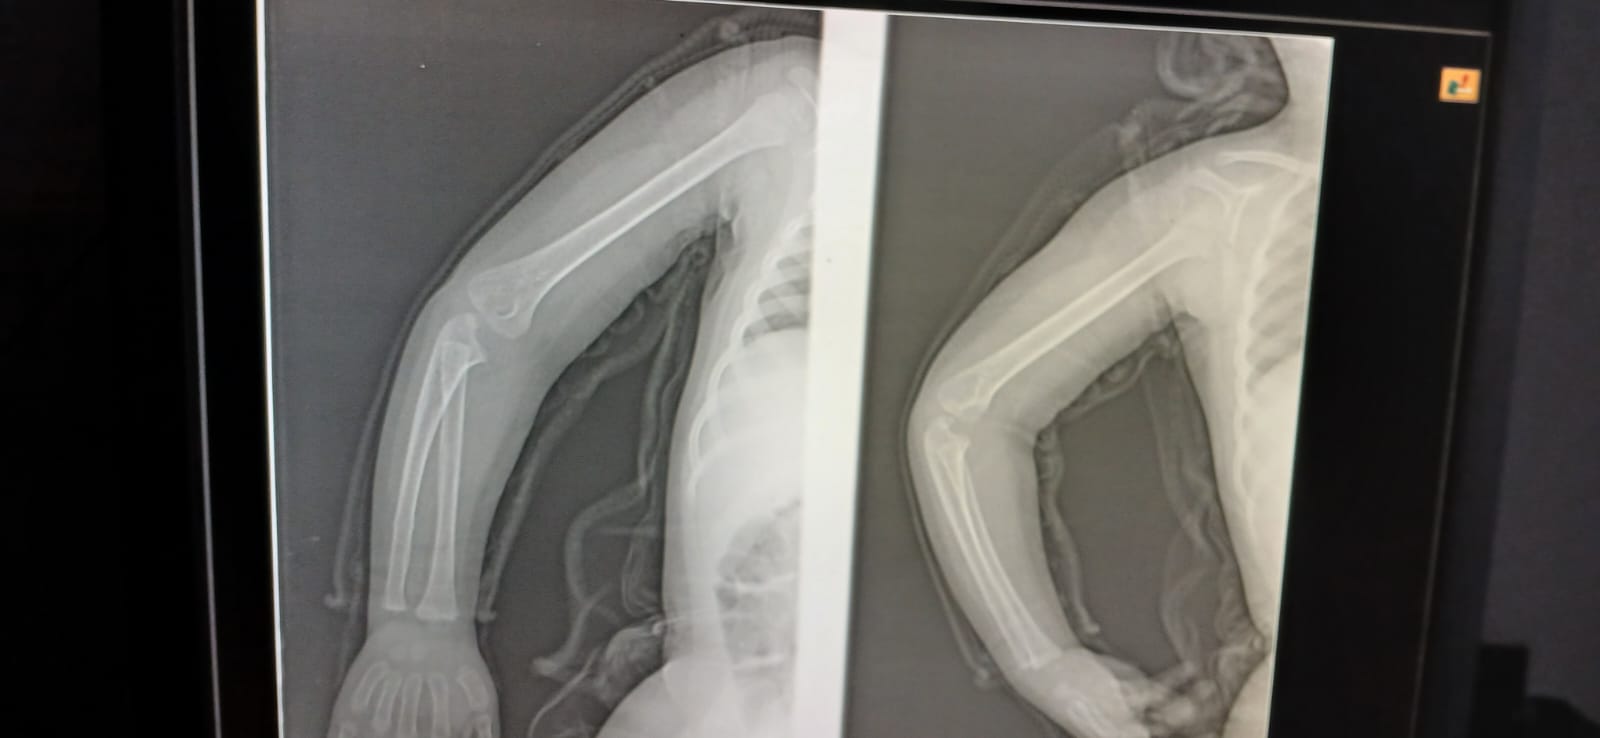

بنتى 3 سنين وقعت على ايدها من الركنه فى البيت

بنتى 3 سنين وقعت على ايدها من الركنه فى البيت في ورم بسيط تحت المفصل والم فى دراعها

WhatsApp Image 2026-03-16 at 9.17.26 AM _1_ WhatsApp Image 2026-03-16 at 9.17.26 AM _2_